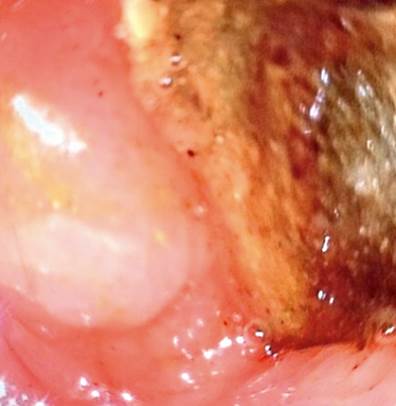

En TACab se evidencia obstrucción intestinal por imagen intraluminal a nivel de la primera porción duodenal de 4,5 x 3 cm (Figura 1 y 2) asociado con neumobilia y presencia de paso del medio de contraste a la vía biliar, lo que cumple los criterios de la triada de Rigler, adicionalmente dilatación de la cámara gástrica secundaria a obstrucción de la luz duodenal y una EVDA con presencia de cálculo impactado en el bulbo duodenal (Figura 3 y 4).

Con el advenimiento de las ayudas diagnósticas y la disponibilidad de las mismas se ha realizado un adecuado diagnóstico prequirúrgico, siendo la tomografía axial computarizada clave, la cual alcanza una sensibilidad y especificidad de 93% y 100%, respectivamente, para el diagnóstico. La endoscopia de vías digestivas altas es muy útil en el diagnóstico de esta patología y es considerada el método de referencia para su diagnóstico, como se demostró en el caso reportado, en donde se realizaron los dos exámenes. Las fístulas bilioentéricas pueden variar entre fístula colecistocólica, colecistogástrica o colecistoduodenal, siendo esta última la más frecuente, con 60% de los casos. Las principales características imagenológicas son presencia de neumobilia, cuerpo extraño alojado en la luz duodenal, obstrucción intestinal con dilatación duodenal y fístula bilioentérica, los cuales concuerdan con la triada de Rigler y se encontraban presentes en nuestra paciente 9,10.